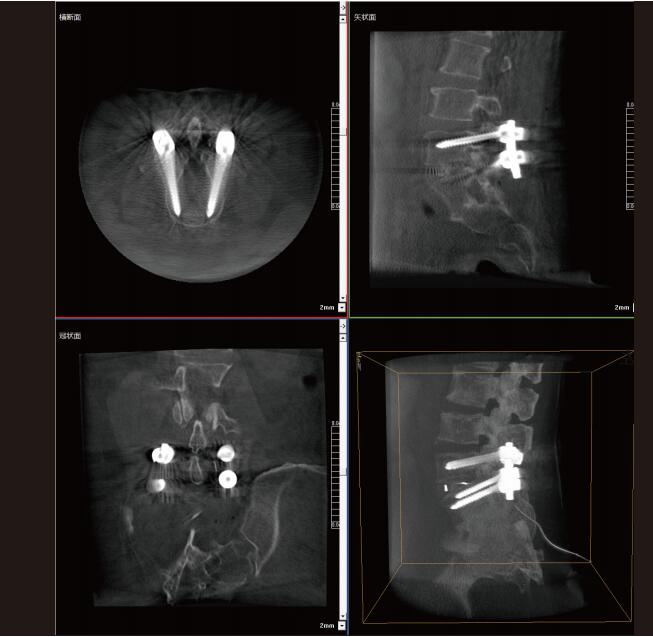

大功率平板三維C形臂PLX C7600術(shù)中實(shí)時(shí)生成:橫斷面、矢狀面、冠狀面及三維影像,可在任意切面、任意角度評(píng)估植入物和解剖結(jié)構(gòu)的相對(duì)位置,在手術(shù)室中即可完成結(jié)果的檢查確認(rèn),適用于全身各個(gè)部位。